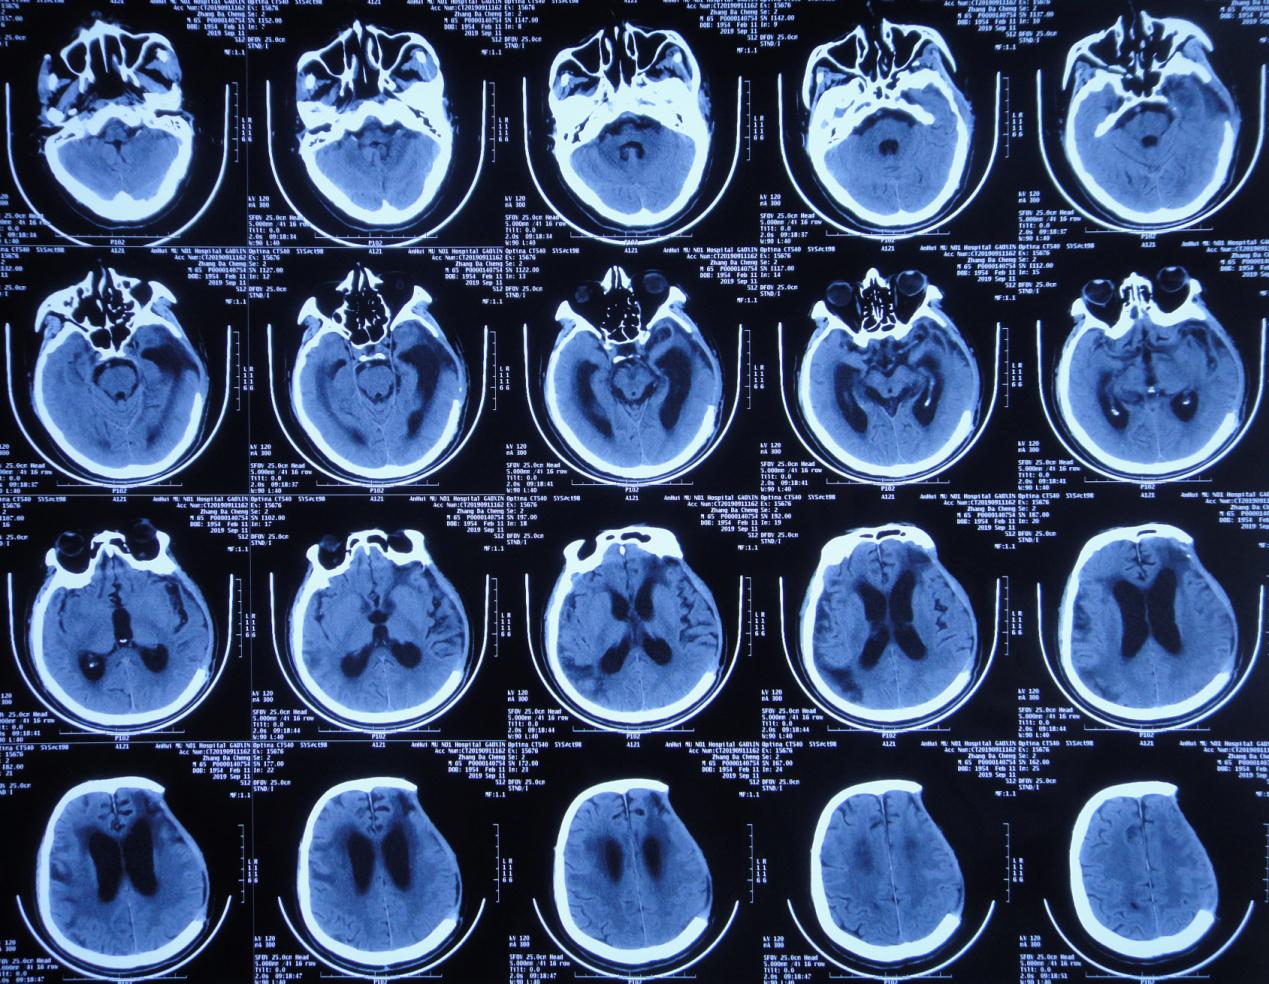

一、李小勇脑脊液科入院前病史

患者2019年7月10日骑电动自行车不慎与大货车相撞,当时意识模糊,可简单对答,四肢可见活动。由120急送至当地安徽省六安市某医院,行头颅CT示大脑多发挫伤(片子丢失),给予甘露醇等脱水治疗,效果差,意识明显加重,呼之不应,呈昏迷状态。当日急转入上级的安徽省某知名省级三甲医院,行头颅CT( 图-1 )示左颞叶脑挫伤伴血肿形成,右额叶脑挫伤,蛛网膜下腔出血,脑疝。

图-1: 2019年7月10日术前头颅CT

当日急诊行“左颞叶血肿清除+去骨瓣减压术”,术后当日复查头颅CT( 图-2 )呈术后改变。术后药物营养脑细胞、降颅压、消炎等治疗。

图-2: 2019年7月10日术后头颅CT